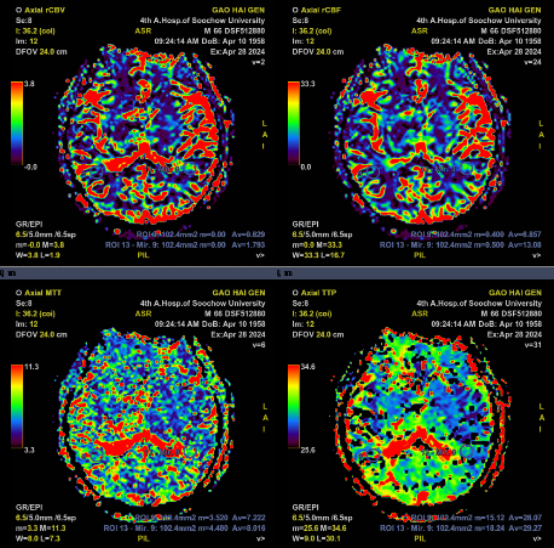

CTA+CTP:右侧大脑中动脉水平段(R-M1)管腔完全闭塞;右侧额顶颞叶缺血性灌注异常

术前PWI:右侧岛叶、颞叶、右侧脑室旁及放射冠区CBF、CBV减低,MTT、TTP较对侧延长

术后PWI:右侧岛叶、颞叶、右侧脑室旁及放射冠区血流明显改善